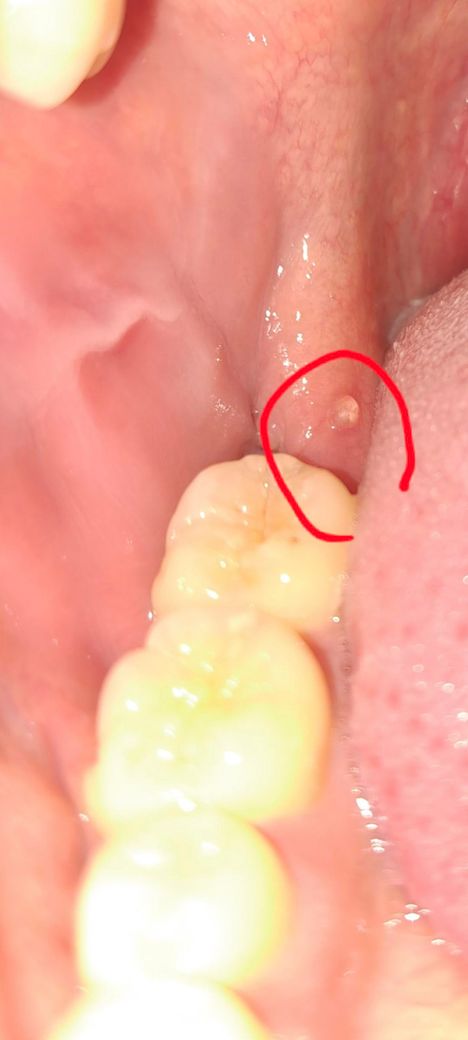

어금니 뒤쪽 물집? 같은게 조그맣게 나있어요...

물집?같은게있어서 톡하고 건드니까 터졌는데 이거괜찮은가요 ㅠ 양치도열심히하고 관리도 잘하고있는데 ㅠ 아프지도않고 그런데 ㅠ

• 1번 째 사진

잇몸이 치아에 씹혓거나 잇몸이 자극을 받아서 생긴거 같으니 그냥 터트리셔도 크게 문제되거나 그런건 없습니다.

단순 수포 같습니다. 크게 걱정하진 않으셔도 됩니다. 전신 건강관리 잘 하시고 스트레스를 줄이고 면역력 키우세요

현재 잇몸에 구내염이 생긴 것으로 보이며, 톡하고 건드니까 터졌고, 통증도 없는 경우에는 크게 문제가 되지 않기에 걱정하지 않아도 됩니다.

염증이 있는 것으로 보이며 원인이 사랑니 일 가능성이 있어보입니다. 치과 가보시는 게 좋겠습니다.